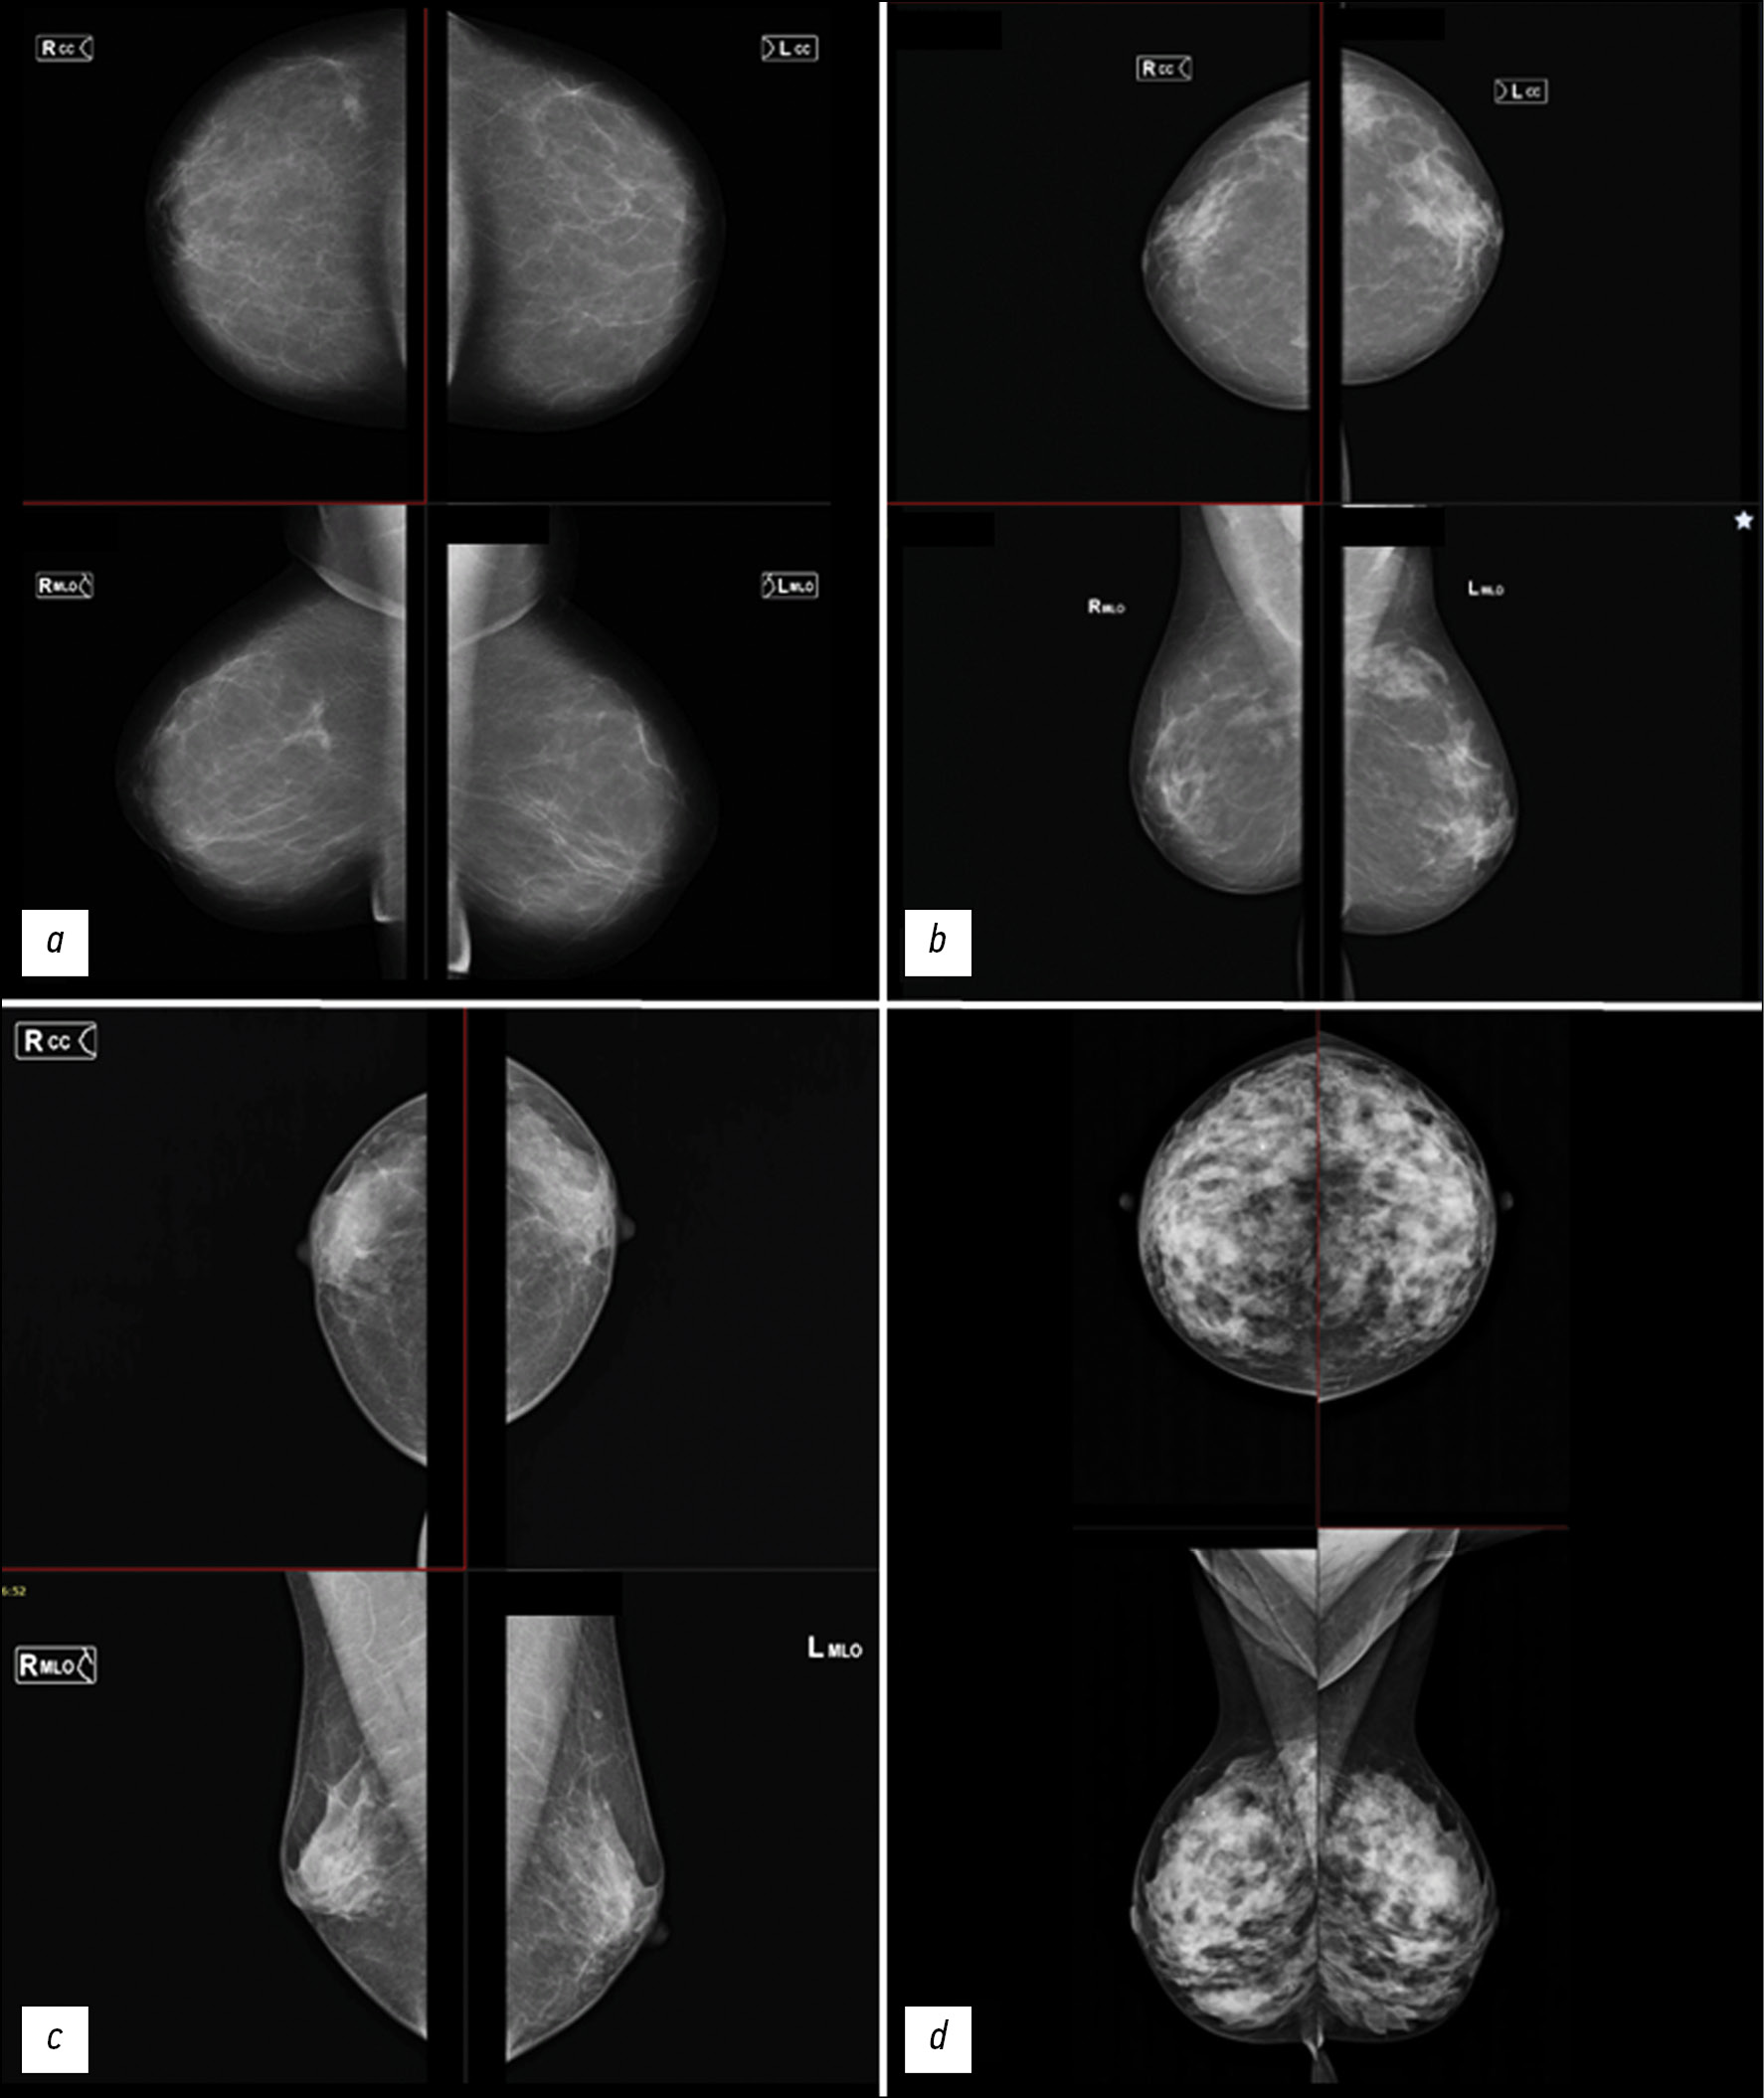

BI-RADS is the most widely used classification for describing radiographic breast density in clinical practice. The types of breast tissue structures are shown in Figure 1.

Fig. 1. Types of breast tissue density according to the BI-RADS classification. For each image, the upper part is the craniocaudal projection, the lower part is the mediolateral projection.